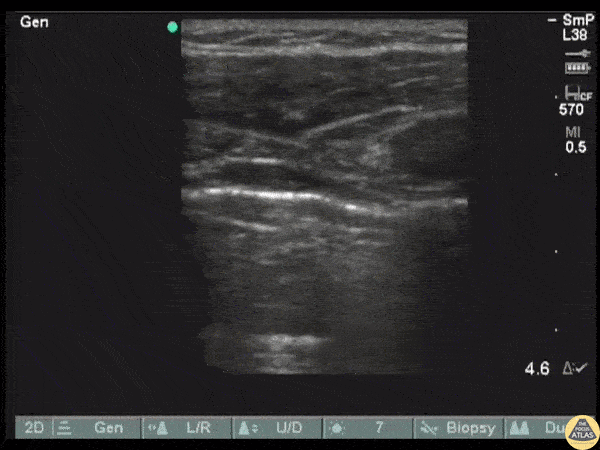

POCUS reveals the return of lung sliding following insertion of a chest tube for pneumothorax. Image courtesy of Robert Jones DO, FACEP @RJonesSonoEM Director, Emergency Ultrasound; MetroHealth Medical Center; Professor, Case Western Reserve Medical School, Cleveland, OH View his original post here